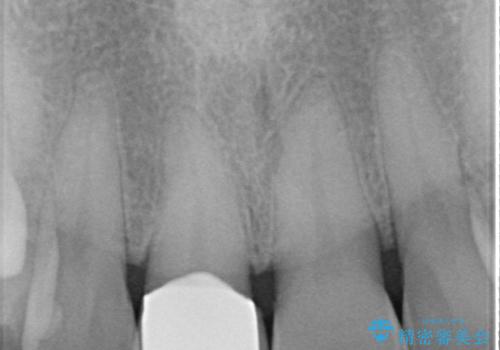

- 前歯を転倒で受傷し、審美性の回復を求めて来院されました。

近医で暫間的なコンポジットレジン修復が為されていましたが、色調に不満があるということでした。

色調の変化が少なく、長期的な予後を見込めるジルコニアクラウンで天然歯を模した審美性の回復を計画します。